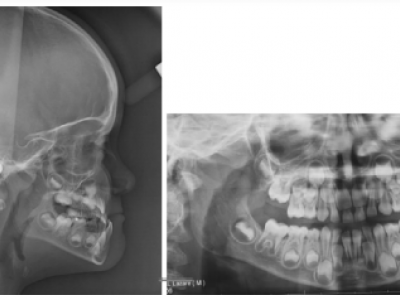

L’occlusion est inversée sur les 4 incisives ; les canines maxillaires, n’ayant pas de place, vont faire leur éruption en ectopie vestibulaire. Ici encore, le manque de développement du maxillaire entraîne un manque de place pour les dents définitives. Les secondes prémolaires ne sont pas encore sur l’arcade (Fig. 18).

Le patient est revu à 22 ans 8 mois (Fig. 21-23), à la demande du praticien, avec un bilan radiologique (Fig. 24).

Les dents de sagesse ont été extraites, les résultats sont globalement maintenus à l’exception de l’articulé 23/33, aucun fil de contention n’a été collé à l’époque pour prévenir les problèmes parodontaux sur les incisives en cas de récidive éventuelle (Fig.25-26).

On note cependant que le maxillaire et l’étage moyen de la face manquent de relief et de volume, par rapport aux cas entrepris plus tôt, chez lesquels, à l’âge adulte, aucune séquelle de la malocclusion initiale n’est décelable sur le visage. L’utilisation d’un arc lingual pour bloquer les 6 dans le traitement de la classe III est peut-être responsable de la mésialisation secondaire de ces dents et du manque de place apparu par la suite pour les canines inférieures.